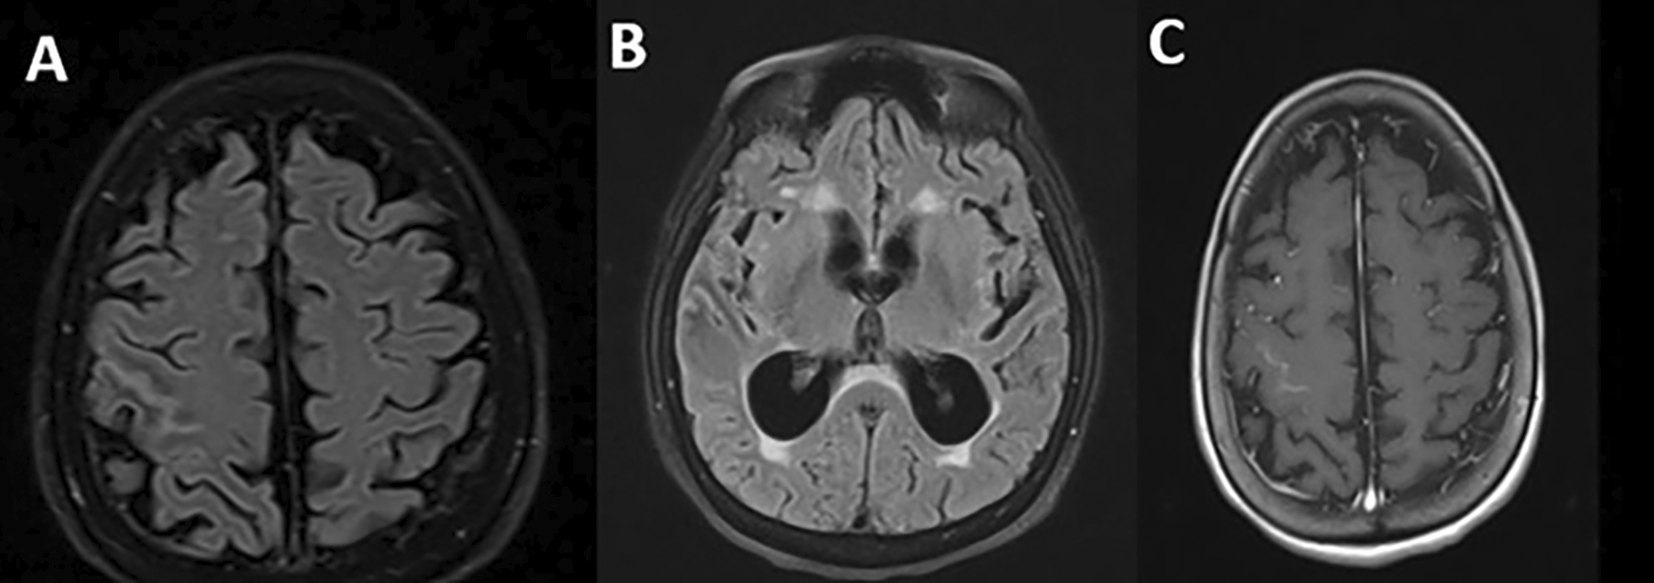

Regarding the imaging studies performed, brain tomography without contrast did not show alterations and brain magnetic resonance imaging showed extensive leptomeningeal gyriform hypersignal in the right precentral sulcus region without mass effect and tenuous contrast uptake, associated with hydrocephalus and transependymal edema (Figure 1).